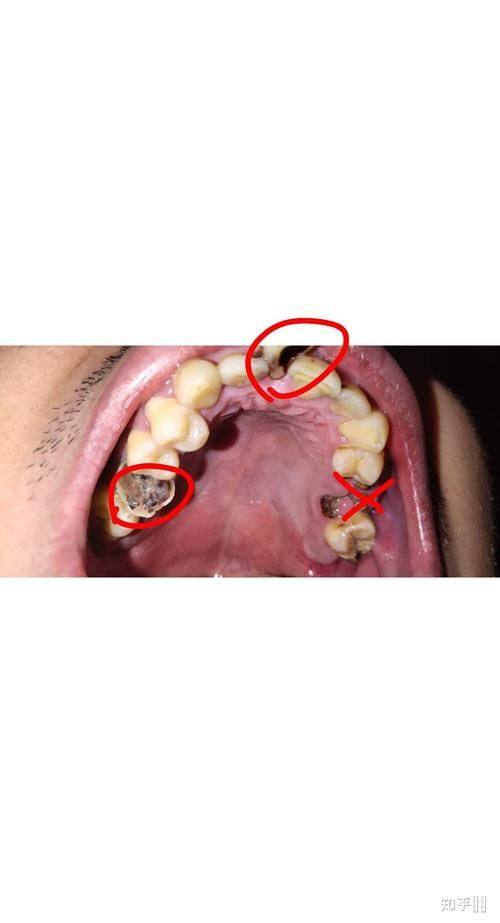

本文围绕如何判断宝宝牙齿是钙化还是龋齿展开,给出5个关键指标。外观上,钙化是浅色斑点、表面光滑,龋齿有黑点、龋洞且表面粗糙;质地方面,钙化基本不变,龋齿会松软;钙化不疼,龋齿会引发疼痛;形成原因分别与营养、疾病和口腔卫生、甜食有关;发展上,钙化慢,龋齿快。建议家长初步判断后带宝宝就医确诊治疗。